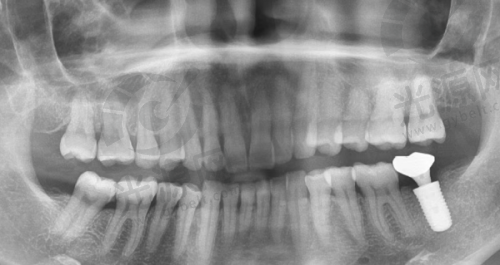

2. 种植牙:依据品牌与材料选择,价格从4599元 - 17000元都有。